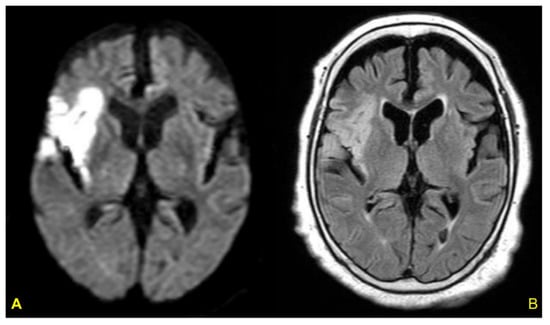

- Nagai, M.; Kobayashi, Y.; Kobatake, H.; Dote, K.; Kato, M.; Oda, N.; Kunita, E.; Kagawa, E.; Yamane, A.; Osawa, A.; et al. Happy heart syndrome: A case of Takotsubo syndrome with left internal carotid artery occlusion. Clin. Auton. Res. 2020, 30, 347–350. [Google Scholar] [CrossRef]

- Osawa, A.; Nagai, M.; Dote, K.; Kato, M.; Oda, N.; Kunita, E.; Kagawa, E.; Yamane, A.; Kobatake, H.; Shiota, H.; et al. A mid-ventricular variant of Takotsubo syndrome: Was it triggered by insular cortex damage? ESC Heart Fail. 2021, 8, 3408–3412. [Google Scholar] [CrossRef]